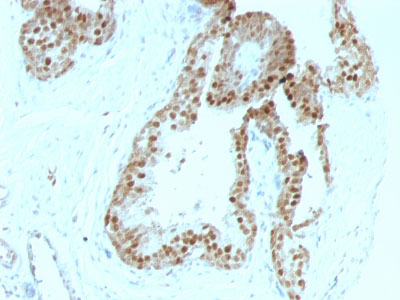

Formalin-fixed, paraffin-embedded human Colon Carcinoma stained with p57 Monoclonal Antibody (KIP2/880).

Formalin-fixed, paraffin-embedded human Prostate Carcinoma stained with p57 Monoclonal Antibody (KIP2/880). |